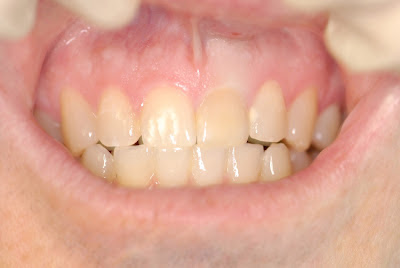

This 41 year old male patient came to our office for a second opinion regarding an implant. In 5th grade he had trauma to his front tooth #9. He had root canal treatment at that time and has never had a problem until 3 months ago.

The discoloration of #9 is very obvious, however, it has never really bothered the patient.